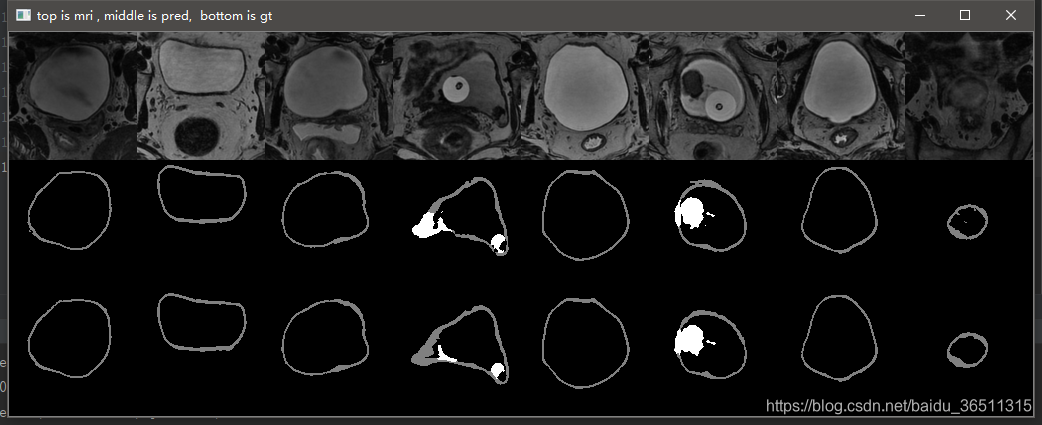

3.10 实验结果

这是笔记本跑了10个epoch的结果,仅仅是测试代码有没有问题。从结果可以看到,代码目前应该是没有问题的,后期只需调参数再训练提升效果即可。

GTX2080TI 跑120个epoch的测试效果:

Val Mean Dice = 0.9051, Val Bladder Dice = 0.9012, Val Tumor Dice = 0.9091